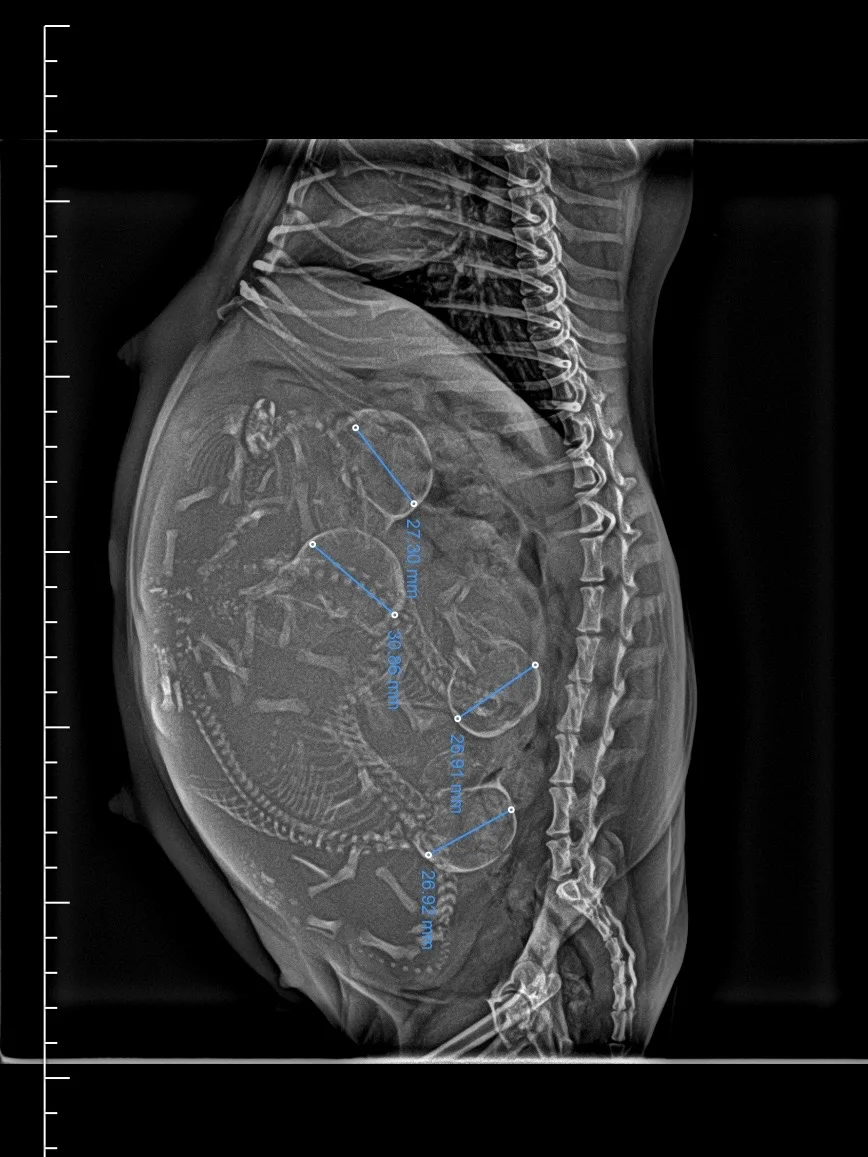

1.20 孕59天,剖腹产3弟弟1妹妹 大哥108克 二弟138克 三妹120 四弟126克